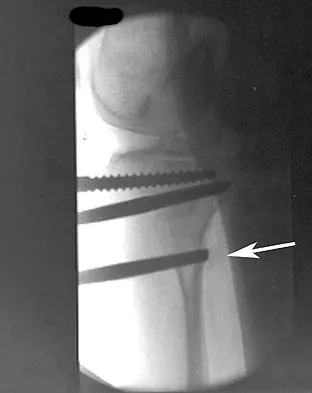

A 12-year-old boy with an ankle fracture undergoes closed reduction under sedation in the emergency department. Figure 27 shows a lateral radiograph of the ankle after two attempts at closed reduction. Based on these findings, treatment should now consist of

Explanation